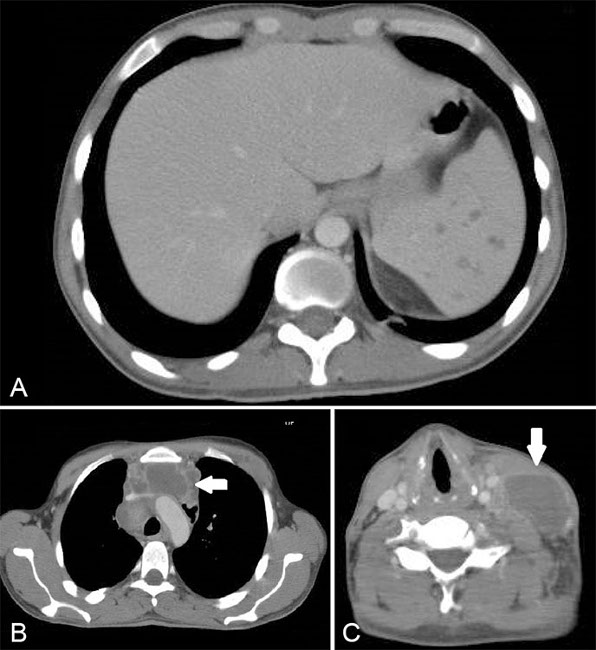

Hombre de 27 años, con VIH, se realizó estudio por tumor cervical al examen físico. Se realiza TC que destacó: (a) múltiples imágenes hipodensas esplénicas compatibles con microabscesos de diámetros fluctuantes entre 1 y 2 cm, de distribución difusa, (b) se observaron grandes conglomerados de adenopatías a nivel mediastínico peritraqueal, subcarinales y prevasculares, alcanzando en ese último un diámetro axial máximo de 8 cm (flecha) y (c) múltiples adenopatías cervicales en ambas cadenas yugulares y en el espacio cervical posterior izquierdo. Ellas presentaron centro hipodenso con realce periférico con el medio de contraste. La de mayor tamaño en el espacio cervical posterior izquierdo midió aproximadamente 4,5 x 2,7 cm en sus ejes transversos máximos (flecha).